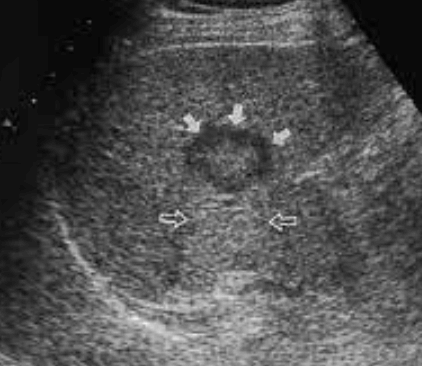

- bull's eys sign (종양 변연에 중심부가 고에코이고 경계부가 저에코인 두꺼운 띠가 보인다)

- cluster sign (종양이 융합하여 분엽모양을 이루어 마치 포도송이 모양을 나타낸다)

US finding

- 동일한 크기의 다발성 종괴가 나타난다.

- 고에코의 다발성 종괴: 대장암이 많으나 위암도 비교적 흔하다.

- 저에코의 다발성 종괴: 유방암, 폐암등에서 나타난다.

- 석회화나 내부 낭성 변성은 전이성 간종양을 시사하는 소견이다.